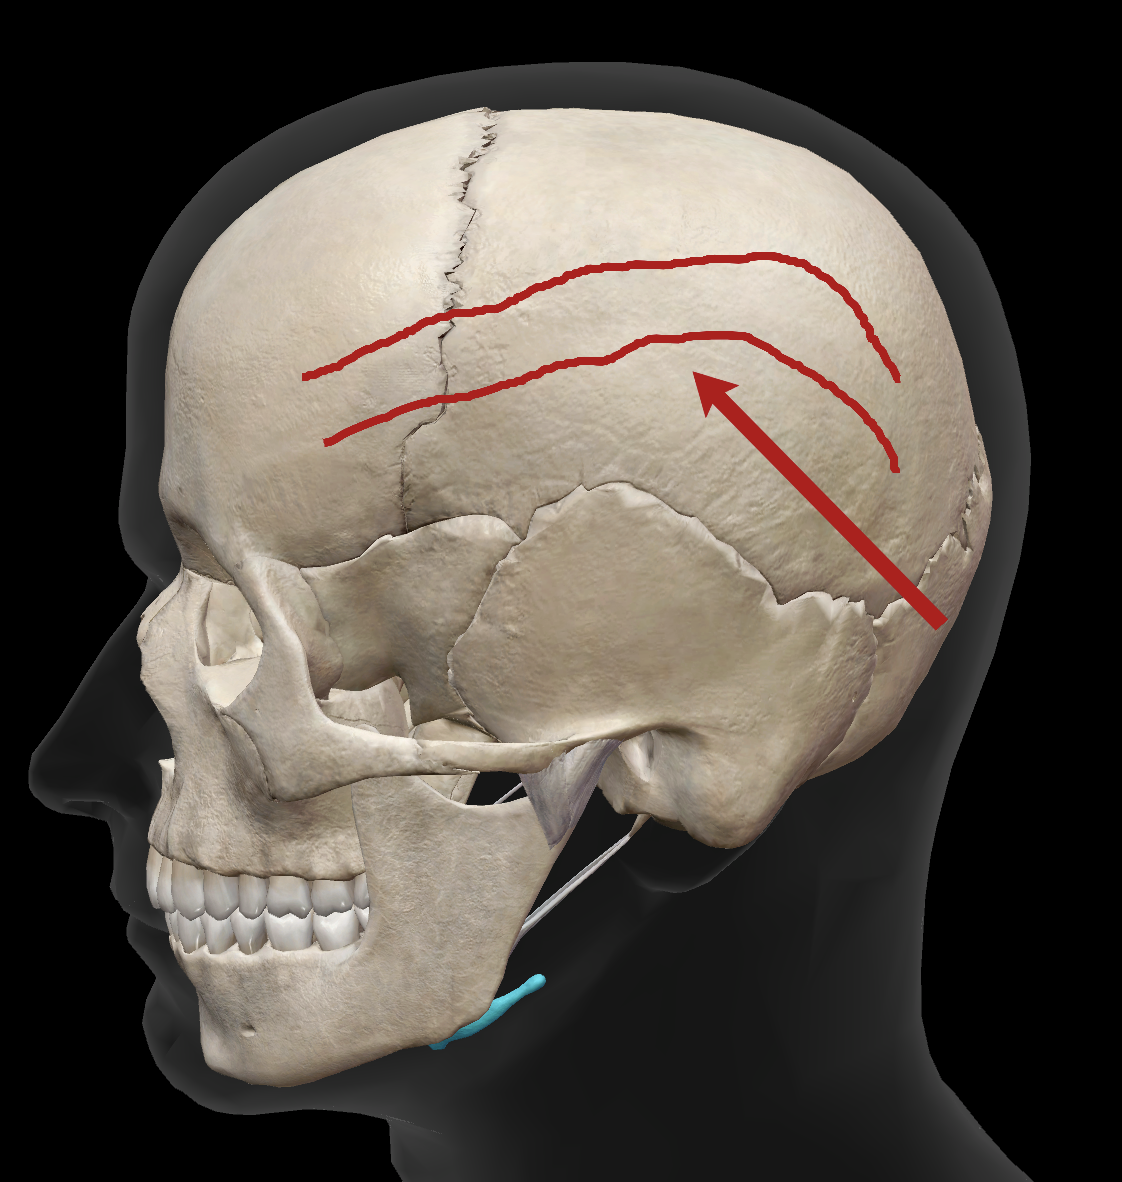

What is the name of this feature?

superior temporal line

What is the name of this feature?

inferior temporal line